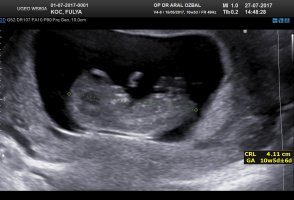

G Gülbaharr@86 Yeni Üye Üye 15 Ağustos 2017 #30 Lütfen cinsiyet yorumu alabilirmiyim...Birkaç foto yükledim ama umarım görebilirsiniz... Ekli dosyalar 20170727145738_740.jpg 92,5 KB · Görüntüleme: 910 20170810111903_604.jpg 84 KB · Görüntüleme: 932 20170810111903_100.jpg 117,4 KB · Görüntüleme: 951